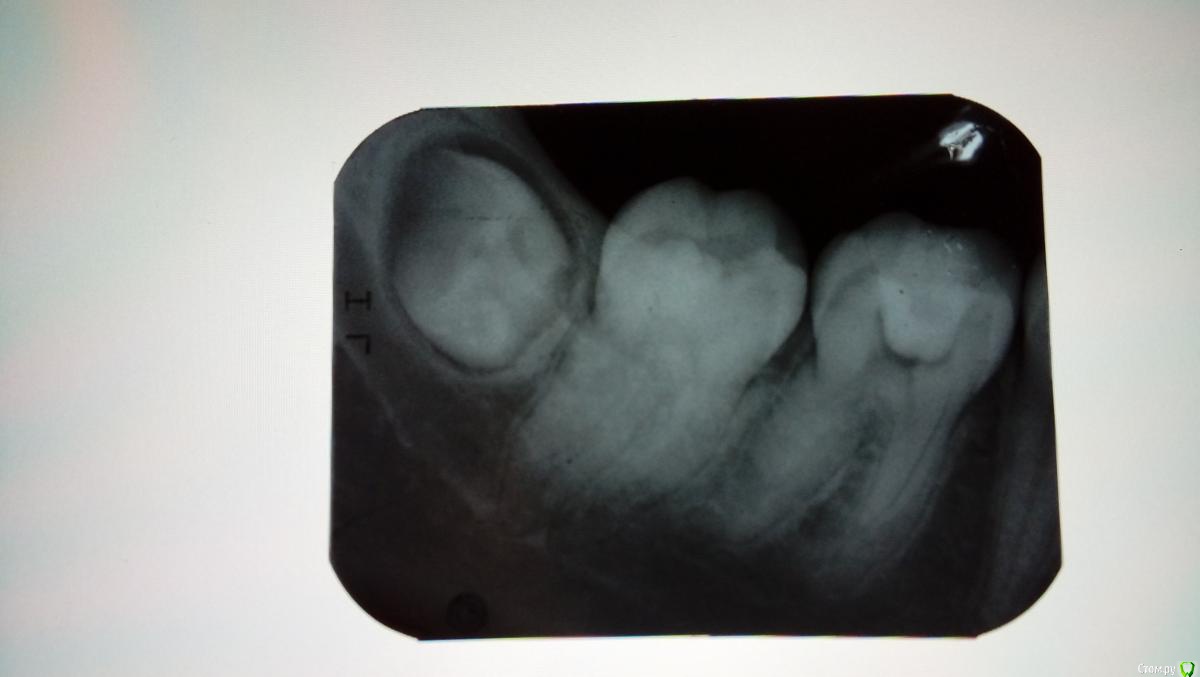

Katerina99 Опубликовано 27 декабря, 2016 Поделиться Опубликовано 27 декабря, 2016 (изменено) Здравствуйте, мне врач лечил зуб и выписал направление на рентген. Что можете сказать о состоянии шестерки и соседних зубов? http://radikal.ru/fp/86ubig91pn2bh Изменено 27 декабря, 2016 пользователем Katerina99 Ссылка на комментарий

Katerina99 Опубликовано 27 декабря, 2016 Автор Поделиться Опубликовано 27 декабря, 2016 Вас сейчас что-то беспокоит? По какому поводу направили на снимок? Небольшой дискомфорт есть и привкус лекарств иногда. Завтра я с этим снимком иду на итоговое лечение. В первый раз мне врач ставил временную пломбу, через некоторое время убрал ее, прочистил каналы, чем-то обработал и заделал новой пломбой с условием, что я сделаю рентген и приду на прием. Ссылка на комментарий

Katerina99 Опубликовано 27 декабря, 2016 Автор Поделиться Опубликовано 27 декабря, 2016 А зуб в цвете не изменен? Ну как сказать? Сброку было темное пятно и, как я поняла, на жевательной поверхности вторичный кариес. Врач убил нерв, прочистил каналы, сделал пломбу и сказал, чтобы я к нему со снимком пришла. Ссылка на комментарий

St. Опубликовано 27 декабря, 2016 Поделиться Опубликовано 27 декабря, 2016 По снимку видно пломбу в полости зуба и корневые каналы без контрастного материала. Ссылка на комментарий

St. Опубликовано 28 декабря, 2016 Поделиться Опубликовано 28 декабря, 2016 Что за контрастный материал?Поясню. Сейчас в каналах корня где раньше был нерв или ничего нет или материал не видимый на снимке,т.е.неконтрастный.Когда каналы пломбируйте постоянно их в подавляющем большинстве случаев закрывают рентген контрастными материалами. За счет этого можно увидеть белые полоски на снимке там где раньше был "нерв" Ссылка на комментарий